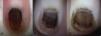

A, The initial dermoscopy revealed the presence of pigmented globules in the nail plate and in the proximal periungual skin. B, Two months later, pigmented globules were visible on a brown background, with narrow and regular longitudinal lines in the nail plate. C, At 6 months the dermoscopic pattern was unchanged.

Physical examination showed practically the whole nail surface to be a homogeneous erythematous-brown color (Fig. 1A). Dermoscopy revealed black globules arranged linearly on the brown background of the nail plate and a marked gray periungual pigmentation with brown globules (Fig. 2A). Correlation of the clinical and dermoscopic findings suggested melanocytic nevus of the nail matrix as the most likely diagnosis, although other melanocytic lesions or hemorrhage could not be excluded at that time. Given the apparent benign nature of the lesion, it was decided to keep the infant under close observation.

Two months later the pigmented area had spread beyond the borders of the nail plate and there was clear involvement of the periungual skin (Fig. 1B). Dermoscopy of this new situation revealed pigmented globules on a light-brown background in the periungual skin, narrow and regular longitudinal lines in the nail plate, and globules of black pigment most numerous in the distal third of the plate (Fig. 2B).

Punch biopsy of the hyponychium was performed and histology revealed a junctional melanocytic proliferation of benign appearance, with melanocytes grouped in nests and as isolated cells in the epidermis (Fig. 3). Histology of a distal fragment of the nail plate showed deposits of melanin. The final diagnosis was periungual and subungual congenital melanocytic nevus (CMN). After 6 months of follow-up the periungual component of the nevus had become more evident but the size of the lesion was unchanged (Fig. 1C and Fig. 2C).